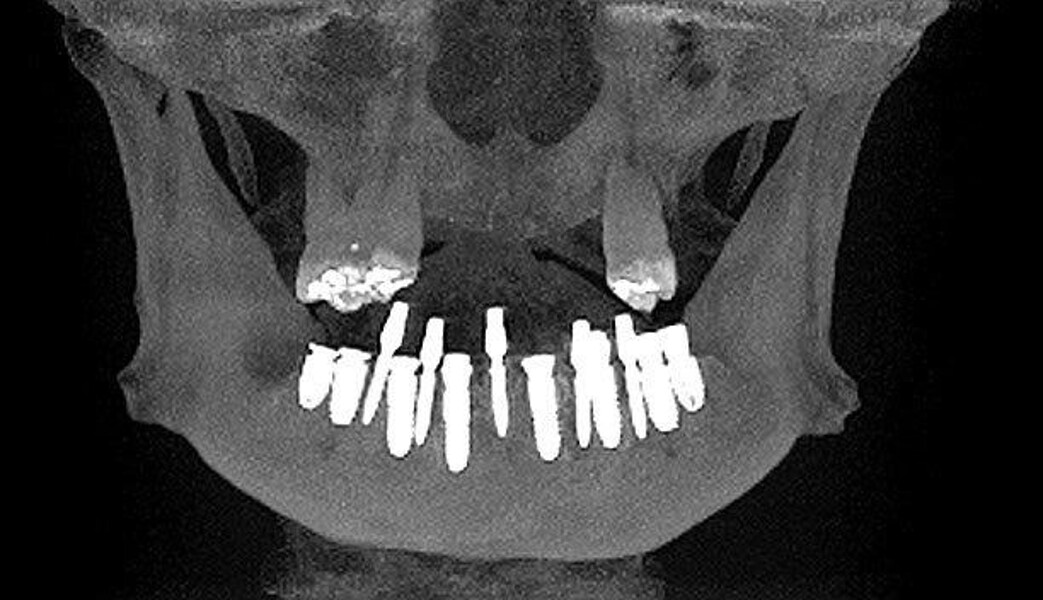

Implantacja z wykorzystaniem szablonu nawigacyjnego 3D